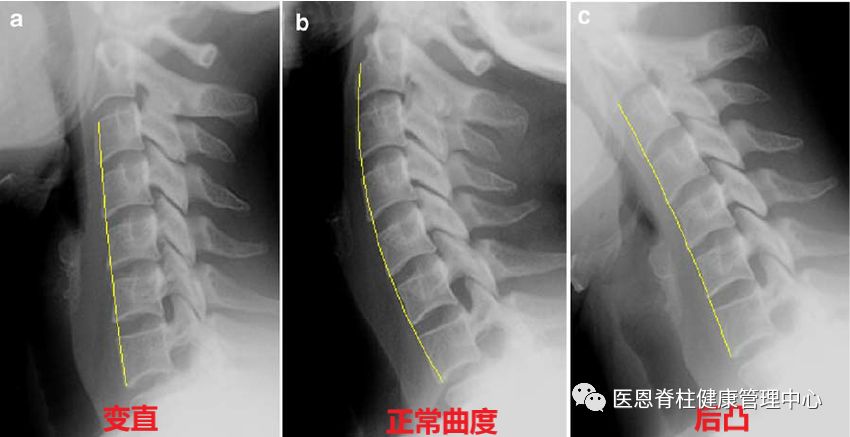

图:中间为正常颈椎的生理弧度,呈前凸

左侧为生理曲度消失,颈椎变直

右侧为颈椎后凸